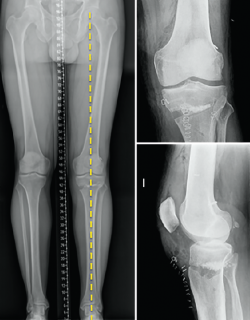

One of the aspects often not adequately taken into account when considering the surgical management of knee instability is the influence of the loading axes upon the instability itself. A varus morphotype or axis associated to anterior instability due to ACL deficit tends to be the most frequent combination.

Effect of varus deformity upon the anterior cruciate ligament

Different studies have shown that deformity of the coronal axis in varus considerably increases loading upon the ACL(40). Mechanical varus of 10º implies an overload of over 400% upon the ACL at 30º of knee flexion or 100% in extension. Minor deviations of the neutral mechanical axis, even slightly above "physiological" varus, such as 5º, already imply an increase in stress upon the ACL (250% at 30º and 68% in extension).

In addition, mention must be made of the high prevalence of meniscal damage associated to ACL lesions(41,42), due to simultaneous damage to both structures, or as a consequence of stress secondary to the instability. Therefore, the combination of varus and anterior instability defines a harmful pattern requiring the consideration of single-step resolution of both situations when marked varus is associated to anterior instability(43).

We should bear in mind that although the indication of osteotomy resides in varus correction (coronal plane), the osteotomy will also affect the sagittal and axial planes (Figure 5).